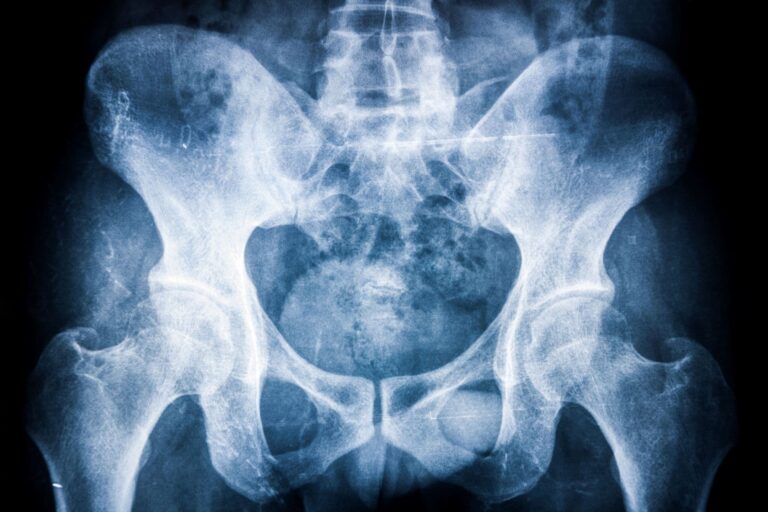

Bechterew-kór (spondylitis ankylopoetica) tünetei és kezelése

A Bechterew-kór (spondylitis ankylopoetica) elsősorban a gerinc ízületeket, illetve a medencecsont és a keresztcsont között található ízületeket érintő gyulladásos betegség, amely idővel akár az alsó végtagi ízületeket is érintheti. Milyen tünetek utalnak a degeneratív megbetegedésre, és hogyan történik a Bechterew-kór…